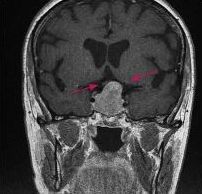

Neue Behandlungsmöglichkeit für kindliche Hirntumore

Glioblastome und ihre neuronalen Netzwerke: Neue Erkenntnisse bieten Ansatzpunkte für Therapien

Überraschender Fund bei Glioblastomen: Inseln potenter Abwehrzellen im lokalen Knochenmark

Hirntumoren bei Kindern: Krebszellen werden auf ihrer Wanderung im Tumor weniger aggressiv

Blockieren eines Eiweißmoleküls macht aggressive Hirntumoren sensibler für Strahlen- und Chemotherapie